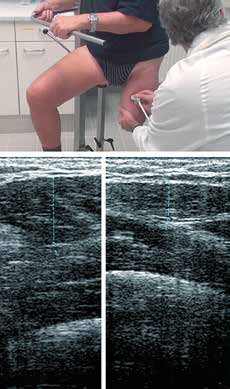

- Die Erhebung sonografischer Daten liefert interessante Auskünfte über den Verlauf der Muskulatur und mögliche Verknöcherungen oder Exostosen.

- Wegen ihrer besonderen Bedeutung sind sonografisch die axialen Muskellücken zu ermitteln und zu kennzeichnen, an deren Position die PBSS-Stumpfstabilisatoren in den Schaft integriert werden (Abb. 5).